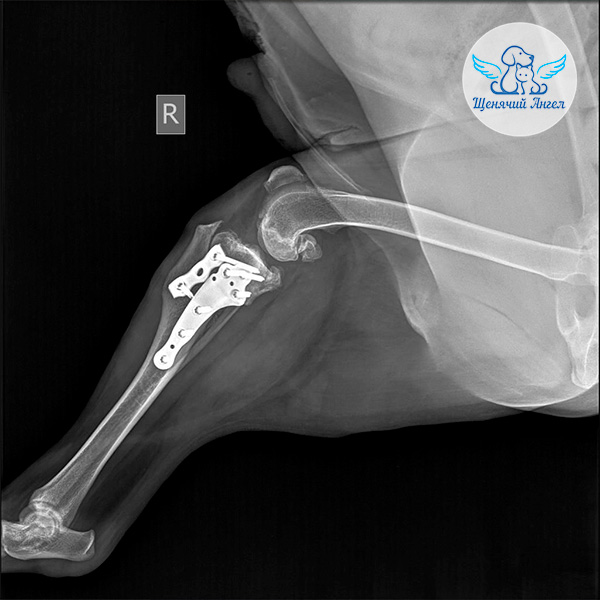

Когда вес снизился до нужных показателей, мы сдали все анализы и получили разрешение на операцию. В ноябре в ветцентре «Медвет» 🏥 хирург Самошкин Игорь Игоревич провёл Батону стабилизацию коленного сустава методом TPLO – современную операцию, при которой изменяется угол большеберцовой кости для устранения нестабильности в колене ⚕️.